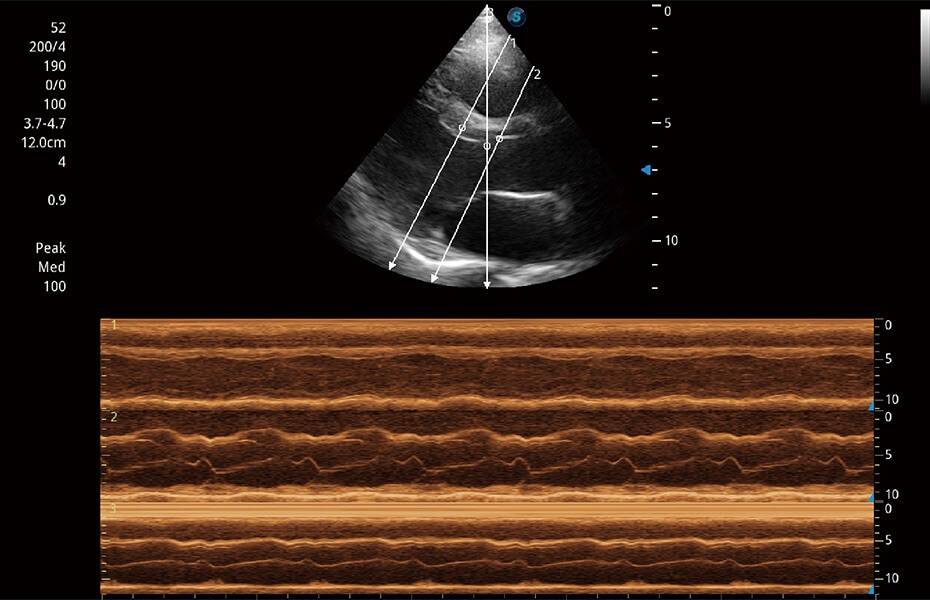

ProPet 60 作为一款高端台式动物超声设备,为动物医生的日常诊断提供了一系列贴合动物临床需求、解决临床实际问题的高级成像功能。凭借全系列高清探头,满足医生对腹部、心脏、生殖、浅表、肌骨等成像的所有需求,切实帮助您提升检查效率,提高诊断信心。

动物是人类最亲密的朋友和最值得信赖的伙伴。开立医疗也一直致力于探索动物专用的超声影像解决方案。 全新推出的ProPet系列,是开立在动物超声影像智能化、专业化、精准化的一次跨越式革新。动物不能用言语来表述自己的不适,通过超声影像,ProPet系列搭建了动物医生与不同物种沟通的“桥梁”,为动物医生注入了“治愈之力”。